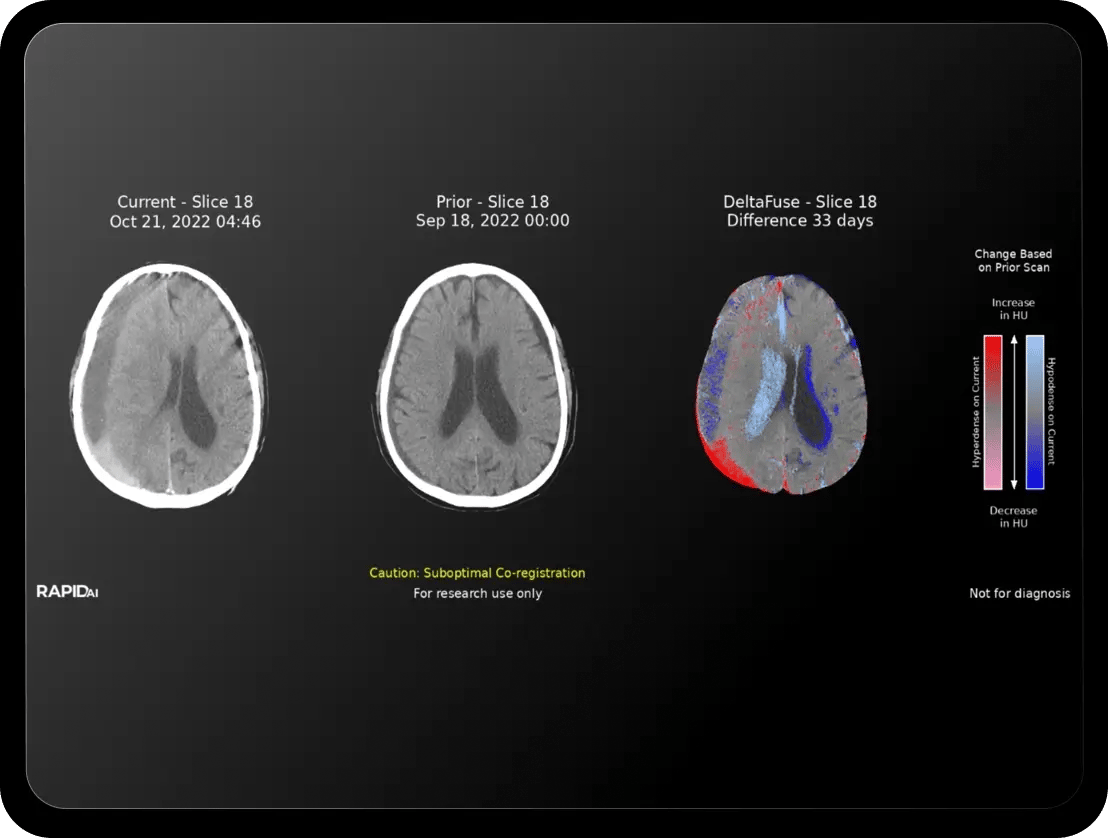

Holistic hemorrhage assessments

Don’t just detect suspected ICH and subdural hematomas, localize and quantify hyperdense tissue.

Triage and hyperdensity– the dynamic duo for fast and accurate bleed assessment